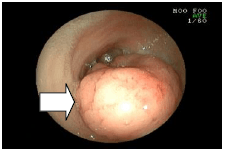

5. 小腸の炎症を調べた例

![]() |

吐き気と下痢が続く猫の小腸の画像です。 炎症が起こり、赤く腫れあがっていました。(矢印) |

炎症を起こしているところをつまんで持ち帰るところです。 持ち帰った部分を調べたところ、リンパ球形質細胞性腸炎という診断がつきました。 |